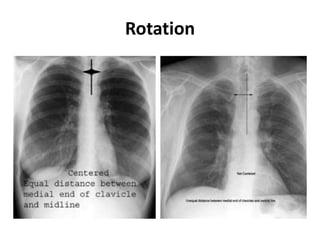

Rotation